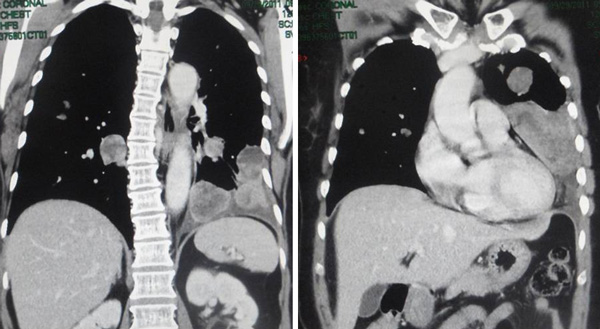

a) … do not allow your doctor to over-test your body with excessive amounts of radiation including excessive CAT scans or PET Scans, which can often make your condition worse by weakening your immune system (page 31),

b) … a single CAT Scan of the chest may be equivalent to 100 plain chest X-ray films and a PET scan performed with a radio-tagged sugar molecule may deliver 5 times the radiation dosage and exposure of a single CAT Scan(page 100),

c) The” gold standard” and most invasive testing is that of the PET Scan, which by radiological standards delivers as much radiation to the recipient as the entire combination of a head, chest, abdomen, pelvis and home scan combined (page 34),

d) The PET scan is based upon the fact that cancer cells, out of necessity rely upon simple sugars for this main source of nutrition. The scan itself uses a radio-tagged sugar molecule to essentially “light up” cancer anywhere in the body, except in the brain tissue which also rely upon sugar as its main source of energy. (page 34),

e) Incidentally, the PET scan is not definitive by any means. A cancer deposit or metastasis must reach a diameter between 5.0 and 10.0 mm before it can even be detected on a PET scan. Therefore, a sizeable amount of cancer could be present in the body and not be detected at all on PET scanning (page 35).